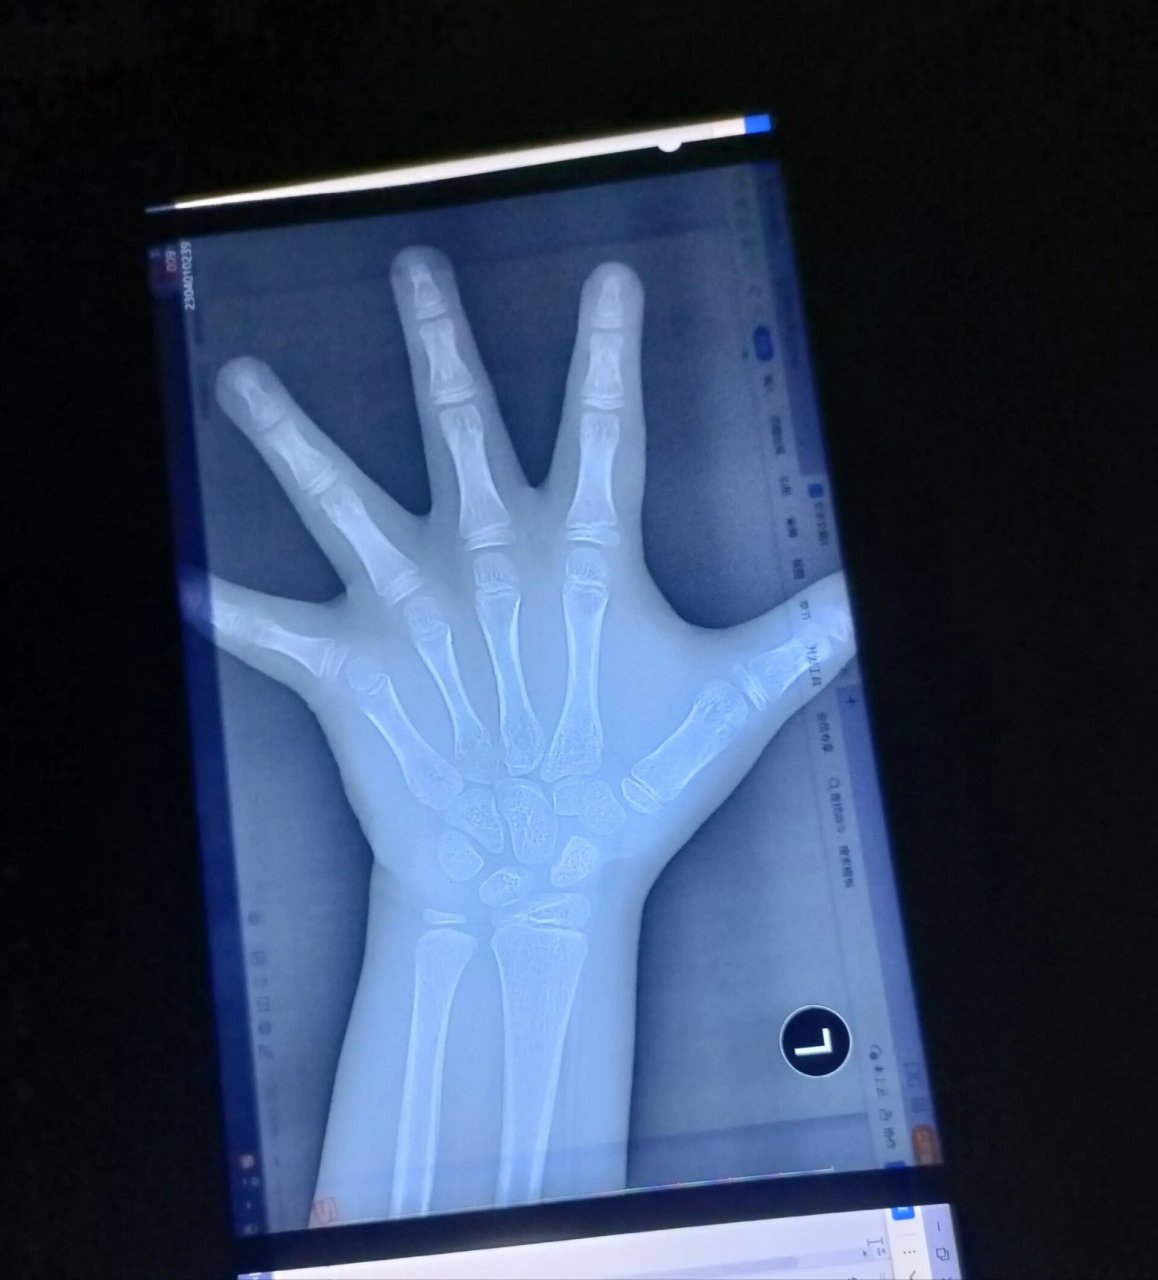

这是一个9岁女孩子的骨龄案例. ·2-5的指骨,骨骺已经盖住了骨干了.

图片尺寸720x960